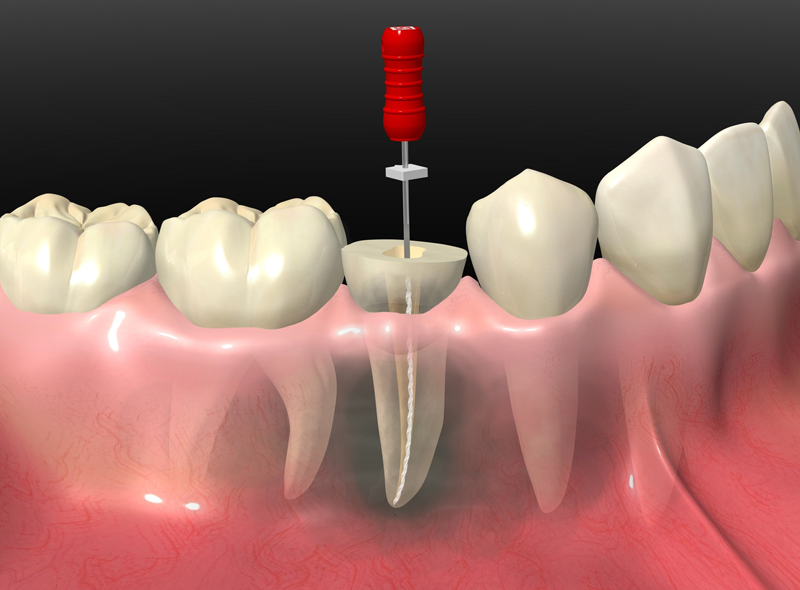

神経までむし歯が達した場合

むし歯が後期まで進行している可能性があります。 当院ではなるべく歯を残すことができるようマイクロスコープを使った根管治療を行っています。

なるべく歯を残す精密根管治療

根管とは歯の神経が入っている非常に細い管です。むし歯で神経を除去した後は根管内に侵入した細菌を除去する必要があり、これを根管治療と呼びます。根管治療がしっかりできていないと根管内で菌が繁殖して再治療することになりますから、非常に重要な治療です。

根管は細いうえに曲がりくねっていることもあるので、肉眼で内部を見ることはできません。そのため、当院ではマイクロスコープを使用して精度が高い「精密根管治療」を行っています。